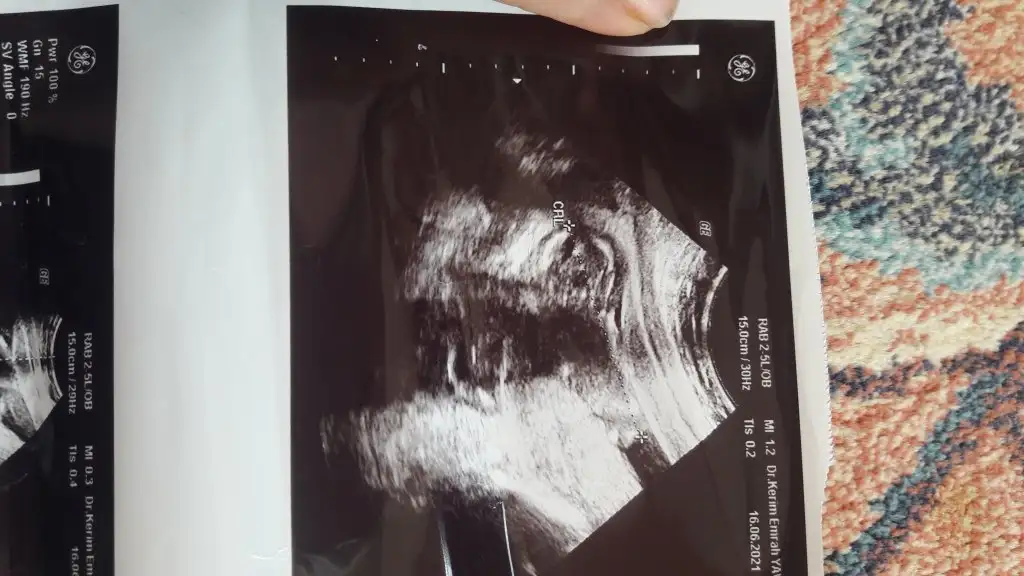

Sanki kız gibi geldi en iyi 11 12 13 haftalar14 haftalık doktor cinsiyeti soylemediEki Görüntüle 2871448

ben hep size özelden attim fotoları nin hic birinde gözükmediSanki kız gibi geldi en iyi 11 12 13 haftalar